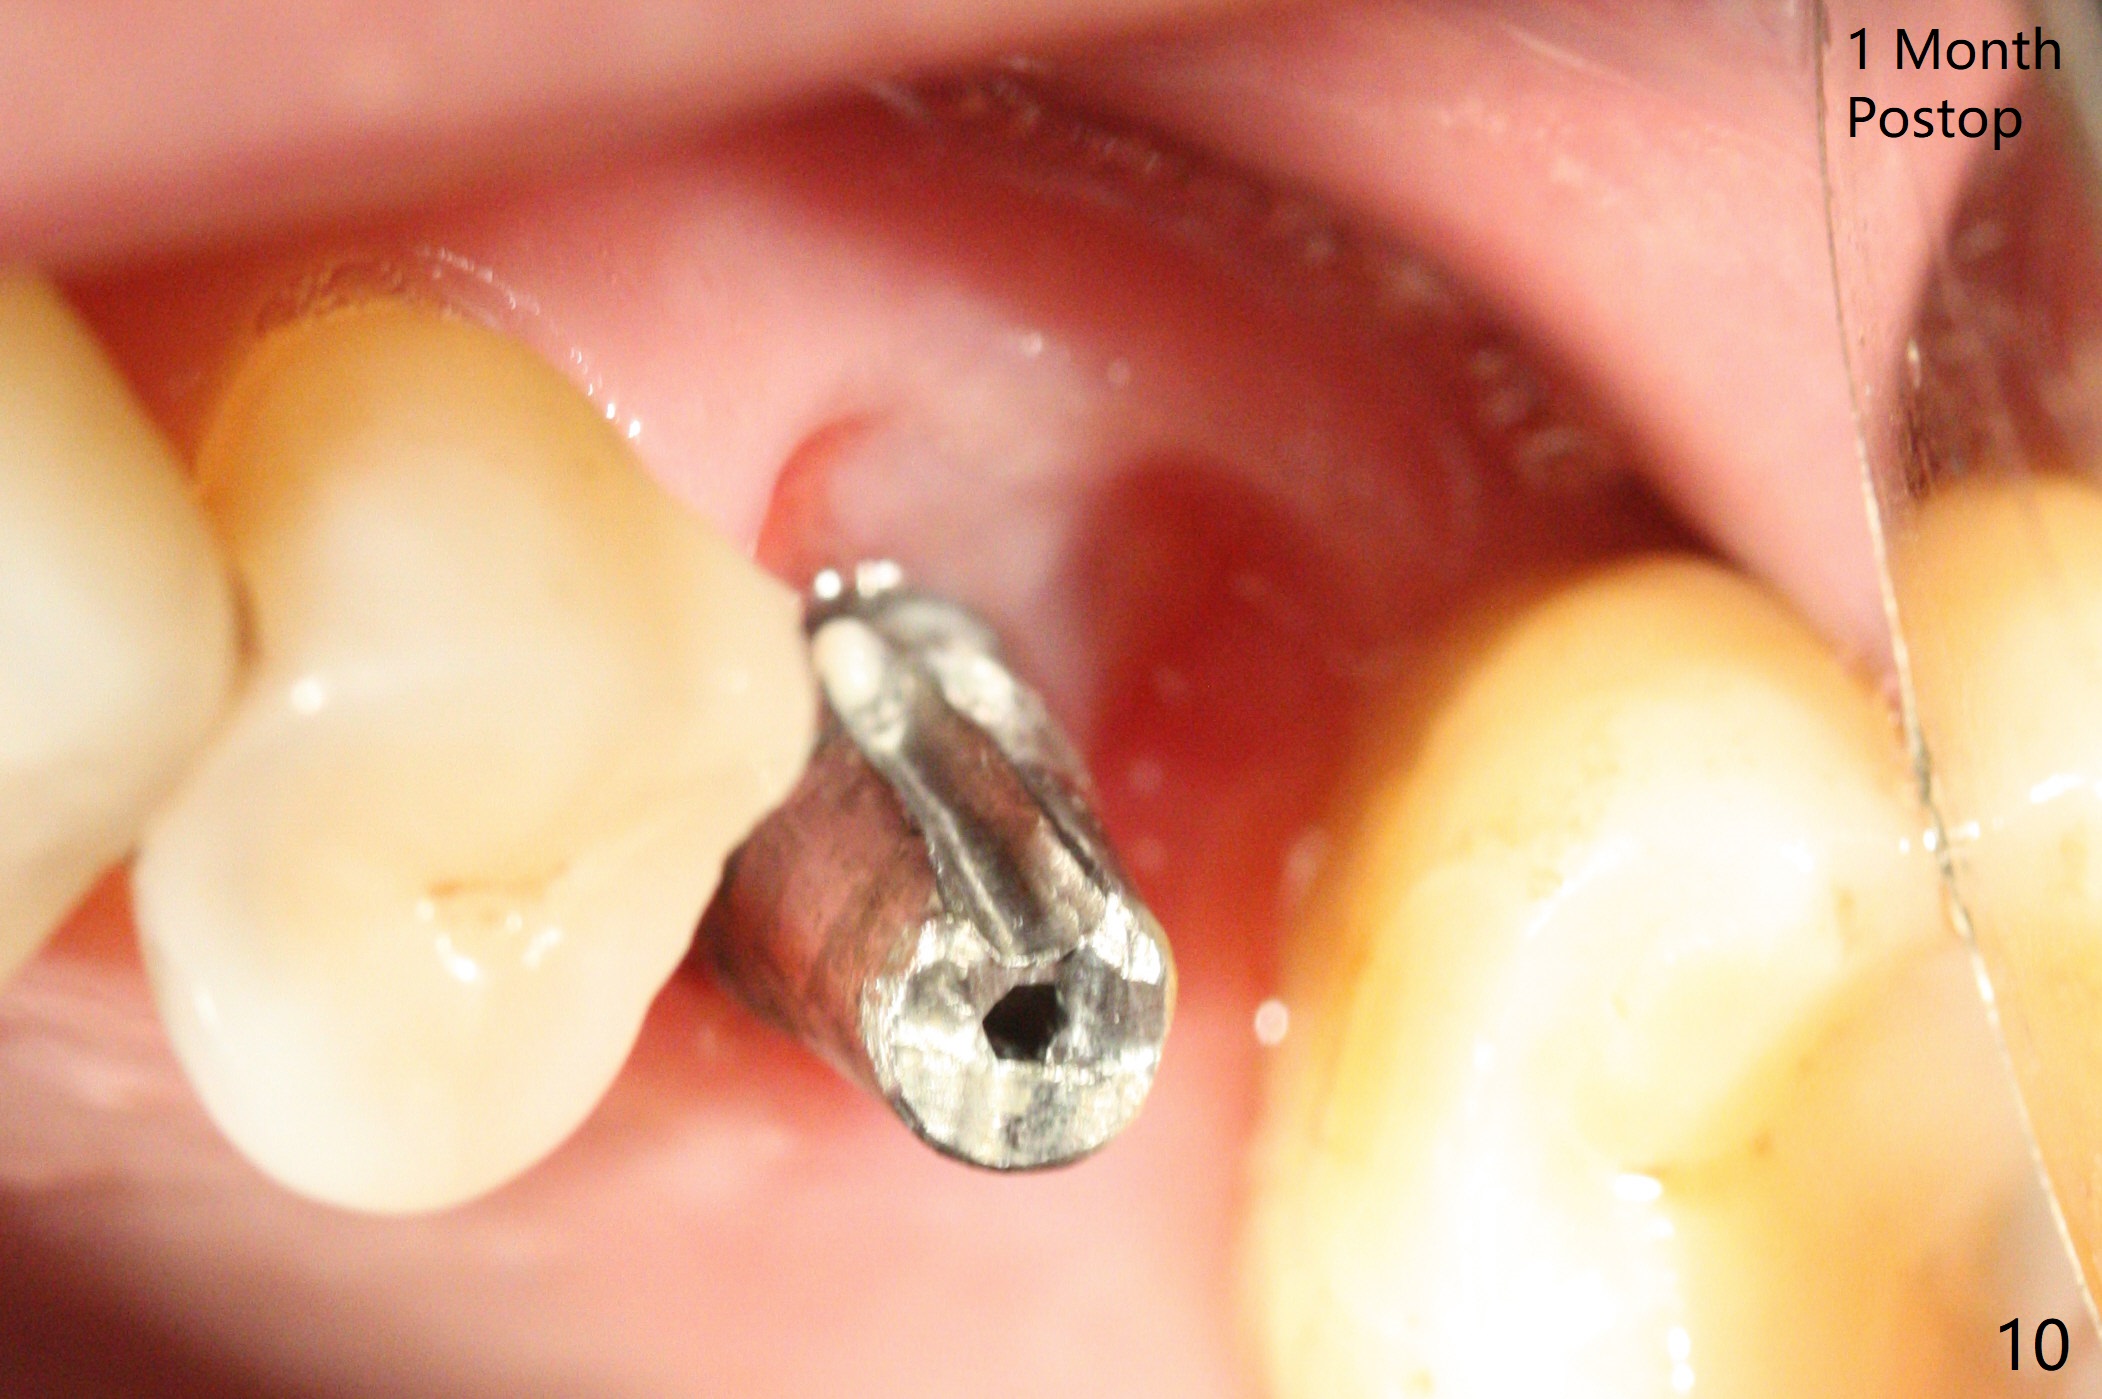

A 65-year-old man had crack tooth syndrome at #14 one month earlier (Fig.1). He shows up with crack and pain in an emergency manner (Fig.2 arrowheads). Preop CT confirms 4.5 mm bone height (Fig.3). Osteotomy will be initiated in the middle of the septum between 3 sockets (Fig.4). Depth of osteotomy is controlled with drill stoppers. After sequential osteotomy free hand, a 5x11 mm tap is used to break through the sinus floor (Fig.5) and sinus lift with Vanilla allograft. To prevent abutment screw loosening, a 5x11 mm tissue-level implant is placed; the distal thread is equicrestal (Fig.6 arrowhead). Following deeper placement of the implant (Fig.7 arrow) with a larger and longer abutment (as compared to that in Fig.6), the margin for an immediate provisional (Fig.9 white curved lines) is prepared in the coronal end of the implant (Fig.8 between arrowheads). With the tissue-level implant, the crown/implant ratio improves. Stress will be partially acting on the implant so that there is less likelihood of abutment screw loosening. The socket heals 1 month postop (Fig.10). The rough surface of the implant is exposed ~ 1 mm. With the margin modified and polished, the provisional returns to place with oral hygiene instruction. It is hoped that the gingiva will cover the exposed rough surface. The buccal rough surface remains exposed 5 months postop (Fig.11). The bone in sinus lift is mature 5 months postop (Fig.12,13). The first 1-2 implant threads are expected to be filled with mature bone in the near future (*). Since the abutment seems long enough for retention, temp bond is used for cementation (Fig.14). Water pik is being applied.